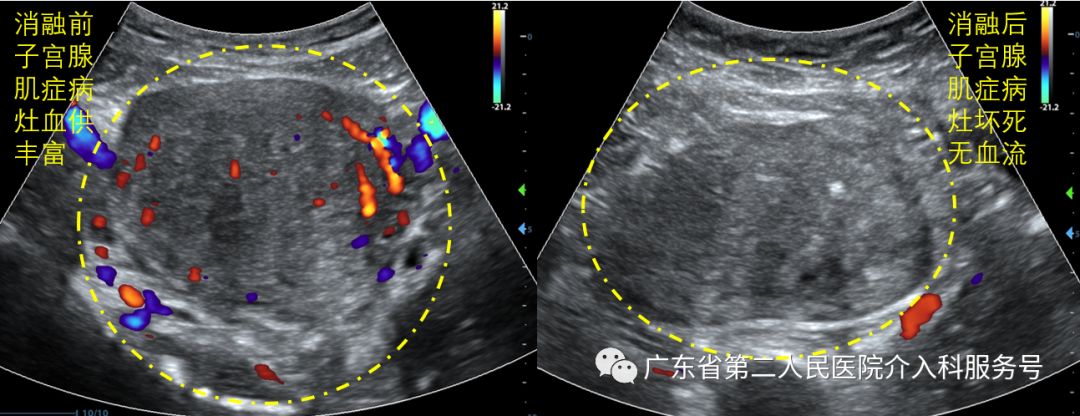

下图为消融前子宫腺肌症病灶的血供丰富与消融后子宫腺肌症病灶凝固性坏死、无血流。

在超声影像实时引导、监控下将针型微波天线经皮穿刺植入至病灶内,利用微波辐射形成的热能,瞬间造成热场内病灶组织的凝固性坏死,病灶组织吸收缩小,同时病灶组织在月经期内不再发生出血,痛经症状得到明显改善或完全消除,贫血状况得到有效纠正的非手术治疗技术。消融治疗后痛经消失及缓解率95.5%,血清CA125测值明显降低,贫血患者治疗后3个月血红蛋白明显升高,对卵巢功能无明显影响,无严重并发症发生,是创伤非常微小而有效的保守治疗方法。